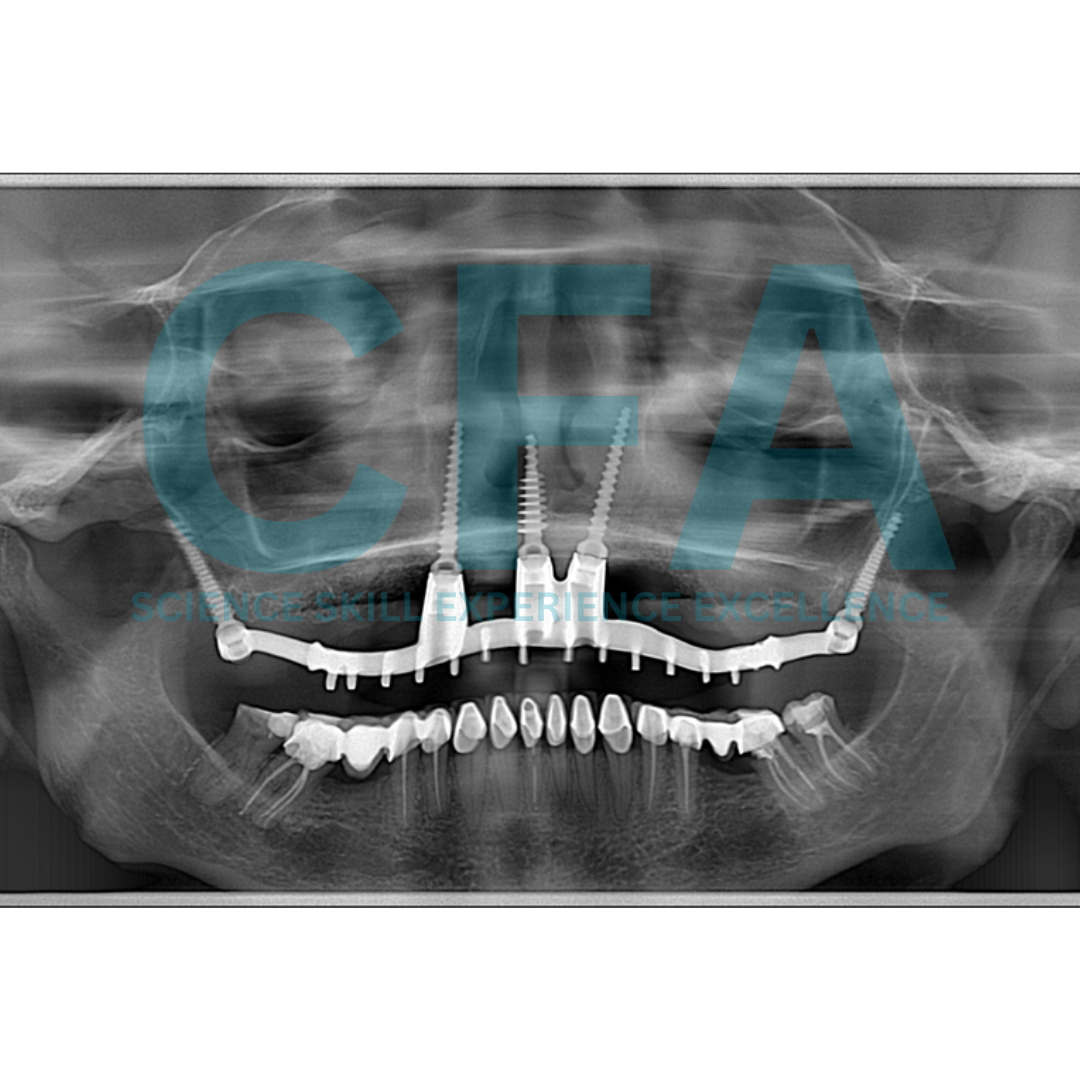

Retreatment of a Failed Quad Zygoma Implant Procedure with Cortically Fixed at once Hybrid Plates: Case Report

Restoration of a severely edentulous arch poses an enormous

challenge to the dentist more so in the maxillary region where

various anatomical structures reduce the option for extensive

surgery. Bone augmentation may be required to enable placement of a sufficient number and length of implants to support an implant prosthesis [1,2]. Retreatment of failed implant further complicates the existing problem because of further loss of bone height associated with loss implant and the presence of scar tissue in the previous operated and implant site which make reoperation difficult. Zygomatic Implants have been used to provide support for oral rehabilitation where there has been a substantial amount of

bone loss from the upper jaw due to resorption or implant failure [3,4].